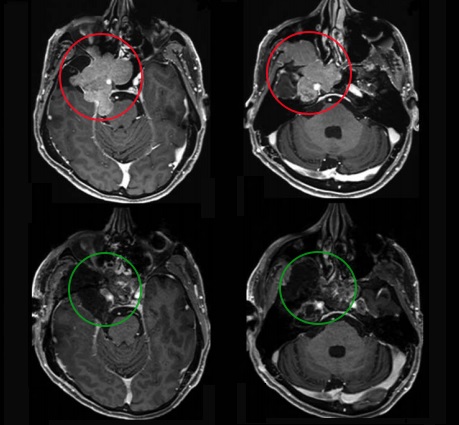

48岁男性较大脊索瘤复发,“双镜联合”成功手术

6岁男孩较大脊索瘤单、鼻孔8mm切口、不开颅成功手术

26岁男士较大颅颈交界区脊索瘤压迫脑干,福教授双镜联合全切巨型脊索瘤

21岁女性颅颈交界区脊索瘤